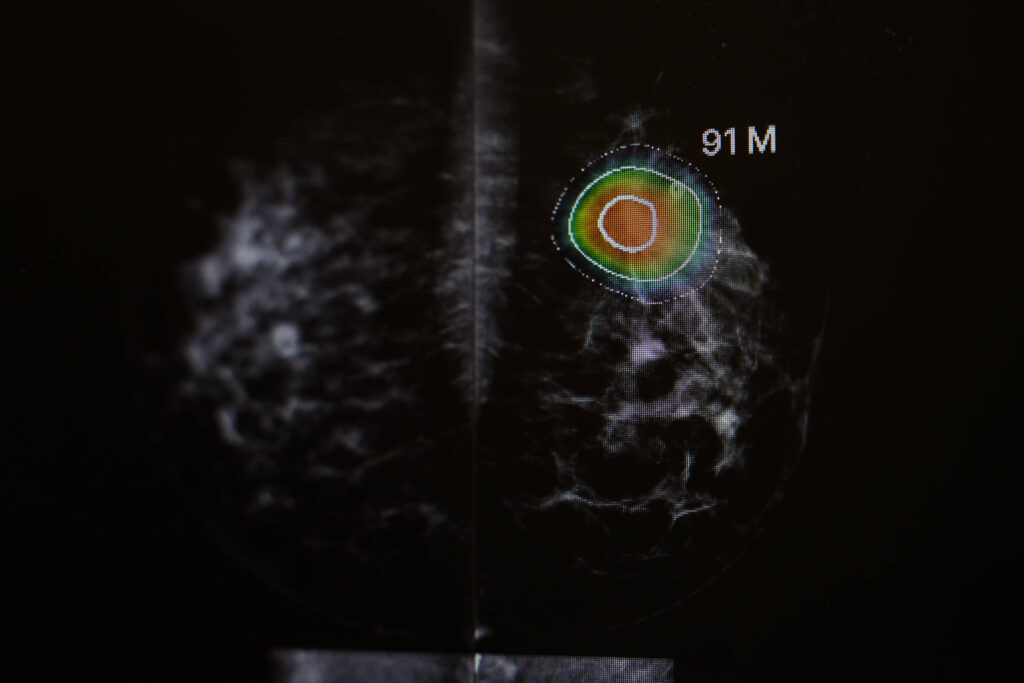

Coordenado pela médica e pesquisadora Kristina Lång, da Universidade Lund, na Suécia, o ensaio clínico comparou dois métodos de rastreamento: de um lado, a prática padrão europeia, na qual dois radiologistas analisam cada mamografia realizada; de outro, um sistema de inteligência artificial que primeiro avalia o exame, encaminha casos de baixo risco para apenas um especialista e mantém a dupla leitura apenas para situações suspeitas. A máquina também funciona como uma espécie de “segundo olhar”, destacando áreas que merecem atenção especial.

O sistema usado no estudo não é uma inteligência artificial genérica, tem nome e dono: Transpara, da holandesa ScreenPoint Medical, já aprovado por agências reguladoras da Europa e dos Estados Unidos. Treinado com mais de 200 mil exames de mamografia de diversos países, o software analisa as imagens e atribui uma pontuação de risco de malignidade em uma escala de 1 a 10, sendo que os casos com pontuação 10 são encaminhados para leitura por radiologistas.

No estudo, o grupo que usou IA teve 82 casos de câncer de intervalo contra 93 no grupo controle. Mais importante: houve 16% menos cânceres invasivos, 21% menos tumores grandes (acima de 2 cm) e 27% menos casos dos subtipos mais agressivos. “Nosso estudo é o primeiro ensaio clínico randomizado controlado investigando o uso de IA em rastreamento de câncer de mama e o maior até o momento sobre uso de IA em rastreamento de câncer em geral”, afirma Kristina Lång.